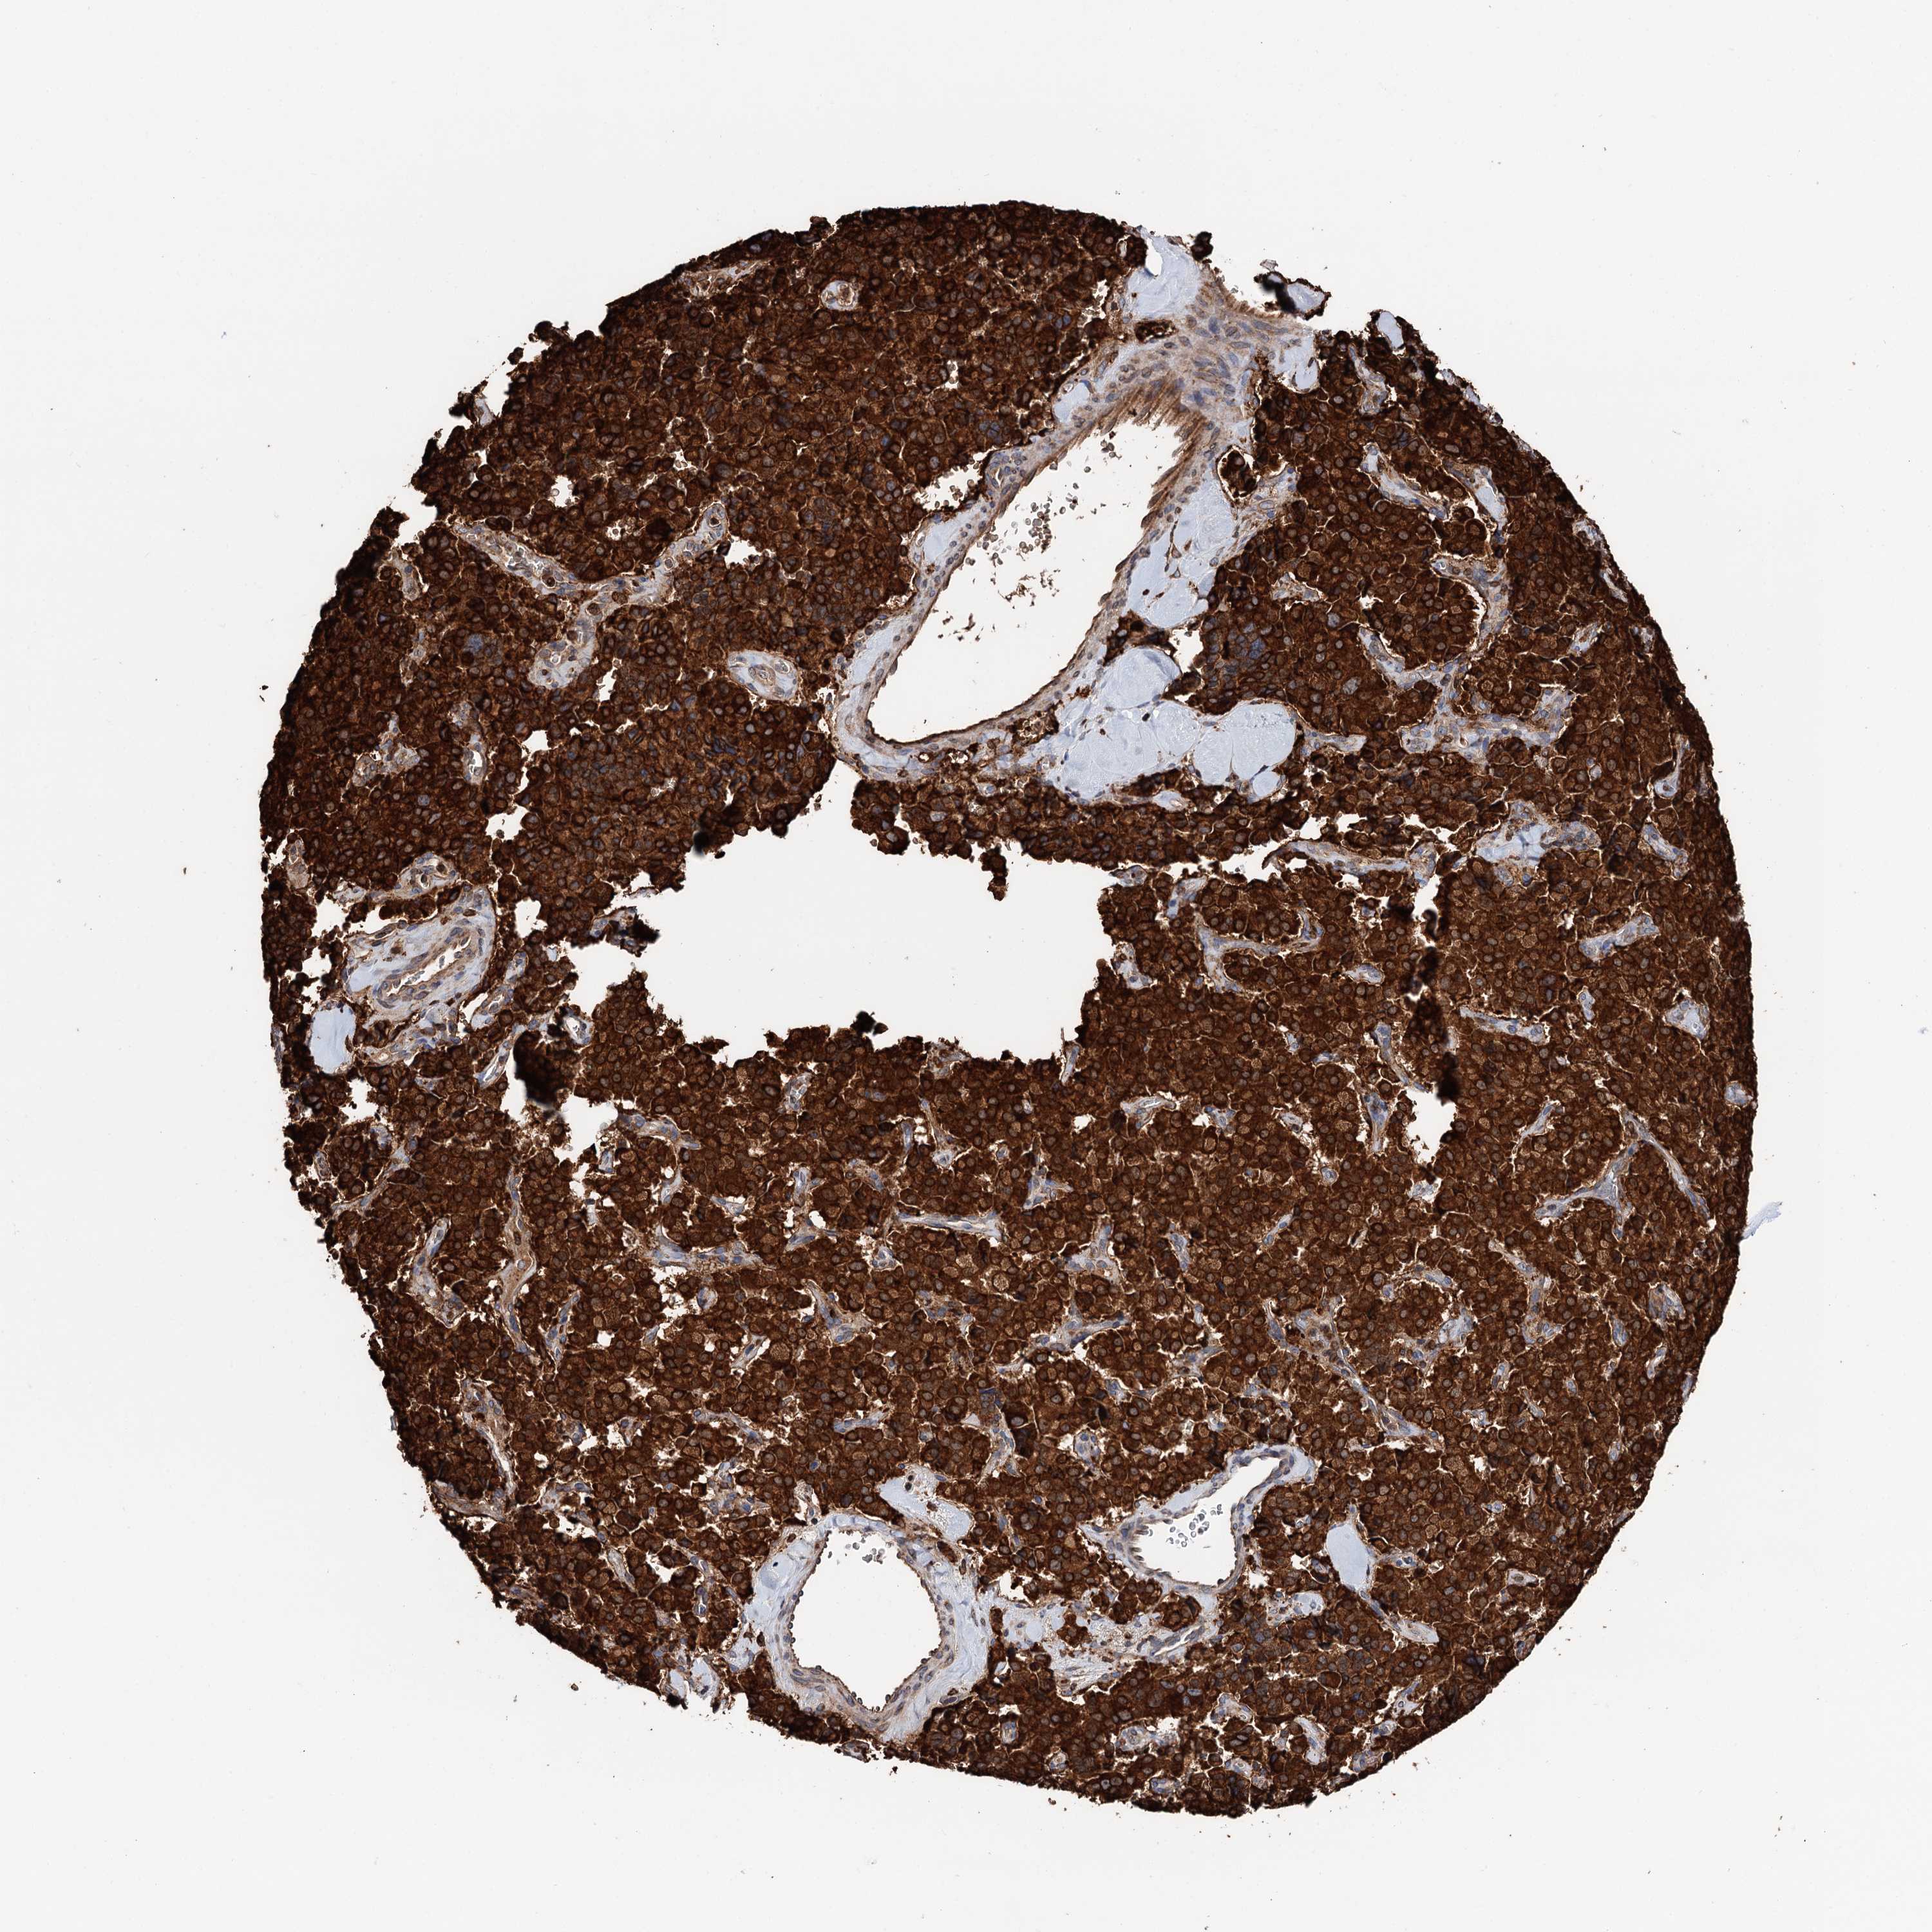

PANCREATIC CANCER - Protein expressioni

A mouse-over function shows sample information and annotation data. Click on an image to view it in a full screen mode. Samples can be filtered based on level of antibody staining by selecting one or several of the following categories: high, medium, low and not detected. The assay and annotation is described here.

Note that samples used for immunohistochemistry by the Human Protein Atlas do not correspond to samples in the TCGA dataset.

Antibody stainingi

Antibody staining in the annotated cell types in the current human tissue is reported as not detected, low, medium, or high, based on conventional immunohistochemistry profiling in selected tissues. This score is based on the combination of the staining intensity and fraction of stained cells.

Each image is clickable and will lead to virtual microscopy that enables deeper exploration of all samples and also displays staining intensity scores, fraction scores and subcellular localization as well as patient and tissue information for each sample.

Antibody HPA039363

Antibody HPA039456

Staining

High

Medium

Low

Not detected

Intensity

Strong

Moderate

Weak

Negative

Quantity

>75%

75%-25%

<25%

None

Location

Nuclear

Cytoplasmic/membranous

Cytoplasmic/membranous,nuclear

Adenocarcinoma, NOS